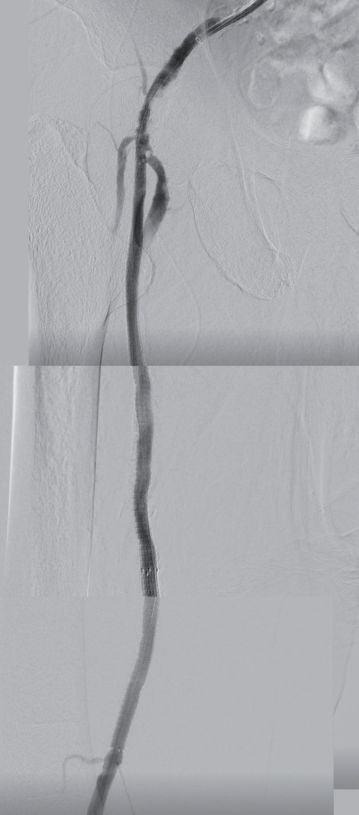

病変長が290 mmと長く、石灰化が高度であったこと、中枢のhealthy landingが10 mm長かったことからバイアバーン® ステントグラフトを選択した。3 mm × 300 mmのバルーンで前拡張するもバイアバーン® ステントグラフトは通過しなかったため、5 mm × 300 mmバルーンで拡張し、さらに0.018 inchのスティッフタイプのガイドワイヤーに入れ替えバイアバーン® ステントグラフトをdeliveryした。末梢にバイアバーン® ステントグラフト5 mm × 150 mmおよび、中枢側に6 mm × 250 mmを留置し病変をフルカバーした。5 mm × 300 mmのバルーンで20気圧まで圧を上げてしっかり後拡張を行った。

IVUSでminimum stent area(MSA)に13.3 mm2と一部の拡張不全を認めたが、血流が良好であったため問題ないと判断した。BKはATA、PTAが閉塞し、PAのみ開存していた。CLTIであったことからBKへの治療介入も検討したが、PAからの側副血行路が良好であったことから介入しなかった。手術時間は147分であった。